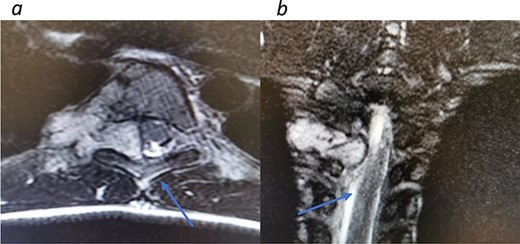

Appropriate tests were done (vanillylmandelic acid and norepinephrine metabolites were found to be slightly high, urine metanephrines were within normal limits, insulin-like growth factor-1 (IGF-1), IGF-binding protein, adrenocorticotropic hormone, cortisol and growth hormone levels were all normal. During her clinic follow-up 6 months post resection, a positron emission tomography (PET) scan showed hypermetabolic activity in the soft tissue at the level of T5 and adjacent right costovertebral junction with possible residual tumor and T5 involvement (Fig. 3). Magnetic resonance imaging was carried out after and showed significant narrowing of the spinal canal at the level of T5 and T6 and focal signal intensity at T5 suggestive of bone involvement (Fig. 4).

A diagnosis of recurrent paraspinal paraganglioma was made and she was admitted for tumor resection. Through posterior approach, laminectomy of T5, lower part of T4 and upper part of T6 was done (Fig. 5). The tumor was exposed and resected along with the parietal pleura. Tumor specimen was sent for histopathology, which confirmed the recurrence of the tumor.

Redemonstrations of tumor post VATS. (a) Axial view tumor noted with arrow causing significant narrowing of the canal. (b) Coronal view of thoracic spine showing involvement of the spinal canal.